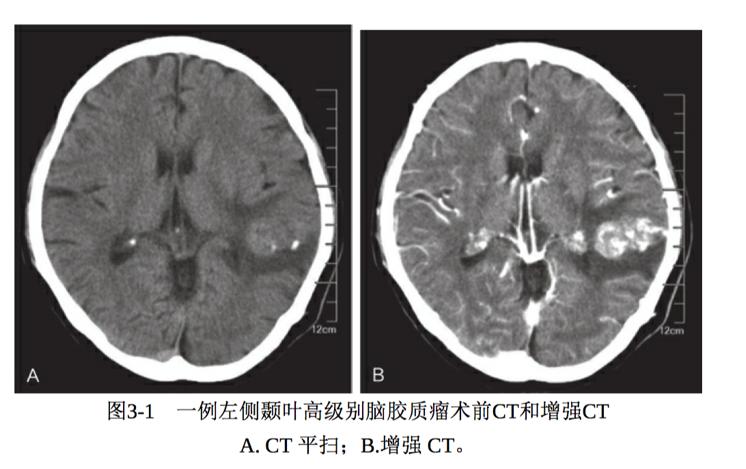

高级别脑胶质瘤CT表现为密度不均,以低密度和等密度的混杂密度为多。低密度为肿瘤的坏死或囊变区域。增强表现为明显强化,呈现不规则的环状强化,强化的瘤壁上可见瘤结节。肿瘤可沿着胼胝体向对侧侵袭,强化表现为蝴蝶状,呈现明显的占位效应,肿瘤周围水肿明显 (图3-1)。